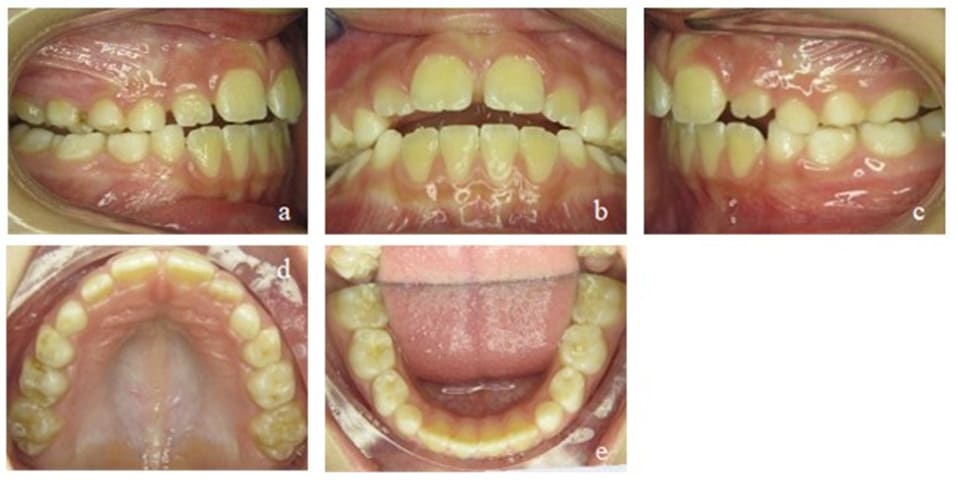

During her first appointment in our orthodontic office, this 8-year-old girl showed an age-appropriate mixed dentition, a bilateral mandibular retrognathism, an increased overjet of 7mm, an increased overbite of up to 80%, moderate crowding in the upper and mild crowding in the lower jaw. Myofunctional, an open mouth resting posture was observed (also described as lip incompetence) which led - in combination with the aforementioned increased overjet - to a resting position of the lower lip behind the maxillary incisors, favoring a large overjet. There were no speech impediments to be diagnosed but during swallowing, activation of the M. orbicularis oris and M. mentalis was observed. The lingual frenulum was short, her body posture normal (Figure 5). The defined orthodontic goals included the overjet and overbite reduction, mandibular advancement as well as elimination of crowding in both jaws. The myofunctional goals were the establishment of a habitual closed-lip position and nasal breathing to provide negative pressure in the oral cavity in order to ensure a physiological resting position of the tongue on the palate.

Orthodontic treatment was performed by using an EGA, chosen according to the occlusal factors and growth deficits of the jaws. Control intervals took place once a month. Directly following every orthodontic control, the patient received myofunctional therapy in the orthodontic office conducted by a specialized myofunctional therapist. After only six months, significant improvements, in both, the occlusal and myofunctional situation could be observed (Figure 6): the overjet was reduced to 3.5 mm, bringing the mandible forward by around ½ of a premolar width. In addition, there was an overbite reduction to 30%, while crowding in both jaws had almost completely been resolved. Due to the EGA and the lip closure exercises, the patient broke the habit of resting her lower lip behind her maxillary front teeth. Nasal breathing had been established in most situations except during physical exertion. The resting position of the tongue and its strength still needed further improvement.

Figure 5: Case 1. Initial findings. En face (a, b) and profile of the patient (c). Frontal view of the occlusion (e), occlusion right (d) and left (f). Upper (g) and lower arch (h). Initial Panoramic x-ray (i).

Figure 6: Case 1. Interims findings after 6 months of treatment. Frontal view of the occlusion (b), occlusion right (a) and left (c). Upper (d) and lower arch (e).